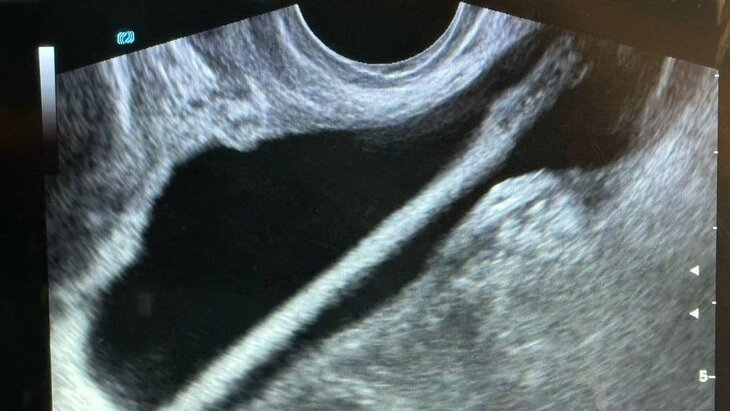

Врачи Красногорской больницы спасли 46-летнюю пациентку, достав из ее мочевого пузыря косметический карандаш, сообщила пресс-служба Минздрава Московской области.

Как рассказал заведующий отделением Петр Сысоев, после УЗИ женщине провели эндоскопическую операцию, в ходе которой инородный предмет успешно извлекли без осложнений. В настоящее время она уже выписана домой.